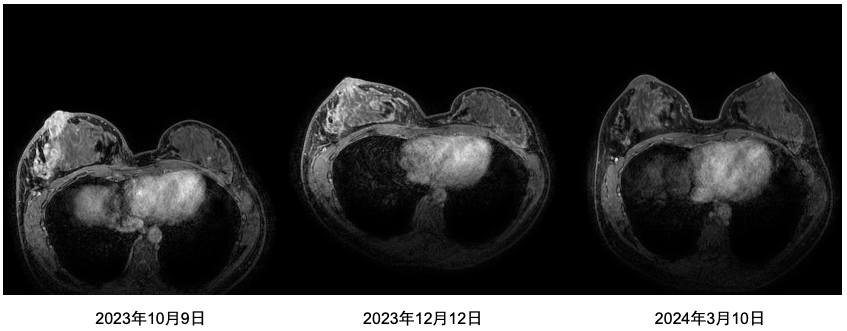

• 乳腺MR(2023年10月9日):右乳中央区及外下象限见两个不规则肿块,右侧乳头及乳晕与肿块分界不清,考虑恶性,请结合临床综合分析(BI-RADS6);右侧腋窝见肿大淋巴结;双侧乳腺内见散在结节状显著强化灶,性质待定(BI-RADS 3)。

乳腺cr是什么双优标杆!从PD到18 个月达颅内CR,瑞波西利改写32岁HR+/HER2-晚期乳腺癌患者命运_https://www.jmylbn.com_新闻资讯_第2张

图 2023年10月9日乳腺MR

疗效评价:乳房部分缓解(PR)。

乳腺cr是什么双优标杆!从PD到18 个月达颅内CR,瑞波西利改写32岁HR+/HER2-晚期乳腺癌患者命运_https://www.jmylbn.com_新闻资讯_第4张

图 乳腺MR对比图

• 乳腺MR(2024年3月10日):右乳外上象限不规则肿块,较前缩小;右侧腋窝见肿大淋巴结较前减小、减少;原右乳腺广泛水肿信号影本次未见显示。

乳腺cr是什么双优标杆!从PD到18 个月达颅内CR,瑞波西利改写32岁HR+/HER2-晚期乳腺癌患者命运_https://www.jmylbn.com_新闻资讯_第5张

图 2024年3月10日乳腺MR